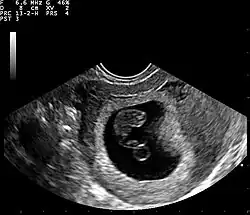

Ultrassom

A Ultrassonografia obstétrica também pode ser usada para detectar e diagnosticar a gravidez. É muito comum um teste de urina domiciliar positivo antes de uma ultrassonografia. Podem ser usadas tanto a abdominal quanto a vaginal, mas a vaginal permite uma visualização mais precoce da gestação. Com a ultrassonografia obstétrica, o saco gestacional (coleção intrauterina de líquido) pode ser visualizado entre 4,5 e 5 semanas de gestação, o saco vitelino entre 5 e 6 semanas e o polo fetal entre 5,5 e 6 semanas. O ultrassom é usado para diagnosticar gestação múltipla, o que não pode ser feito apenas pela presença de hCG na urina ou no sangue.[15] A determinação da idade gestacional do embrião/feto é outro benefício do ultrassom em comparação aos testes de hCG.[16]